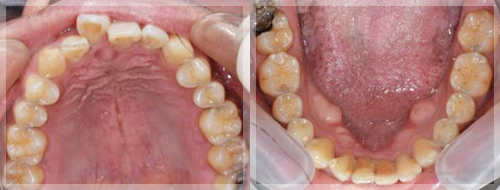

症例6. 被せ物で咬合挙上した症例

![]() ![]() |

![]() |

主訴:歯が常に当たって痛い、噛む位置が分からない

治療方針

マウスピースを使って正しい噛み合わせを確認し、習慣化させるための診査診断が行われます。口腔内反映とは、マウスピースを装着した状態での正しい噛み合わせを意味し、マウスピースを外すと元の悪い噛み合わせに戻ってしまいます。そこで、仮歯や仮の詰め物を使用して噛み合わせを調整し、マウスピースを外しても正しい位置で噛み合うようにします。

最終的な補綴物として、セラミックやジルコニアなどの素材で被せ物を製作し、治療を完了させます。